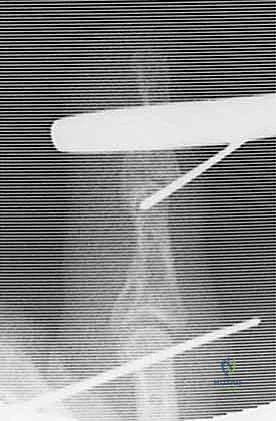

5. تجميع الإطار الديناميكي (Frame Assembly)

يقوم الدكتور هطيف بثني الأسلاك المعدنية بمهارة هندسية لتشكيل الإطار الخارجي. هناك عدة أنواع من الإطارات (مثل Suzuki Frame أو Compass Hinge). يتم توصيل الأسلاك ببعضها باستخدام أربطة مطاطية معقمة (Rubber Bands) أو نوابض طبية. هذه المطاطات تولد قوة شد مستمرة تسحب المفصل وتمنع احتكاك العظام المكسورة ببعضها.

6. الاختبار داخل غرفة العمليات

لا تنتهي العملية بمجرد تركيب الإطار. يقوم الدكتور هطيف بثني وفرد إصبع المريض تحت جهاز الأشعة للتأكد من أمرين:

* المفصل يتحرك بسلاسة دون أي إعاقة.

* السطح المفصلي يبقى في مكانه الصحيح (Concentric Reduction) طوال القوس الحركي، ولا يحدث أي خلع أو احتكاك للقطع المكسورة.